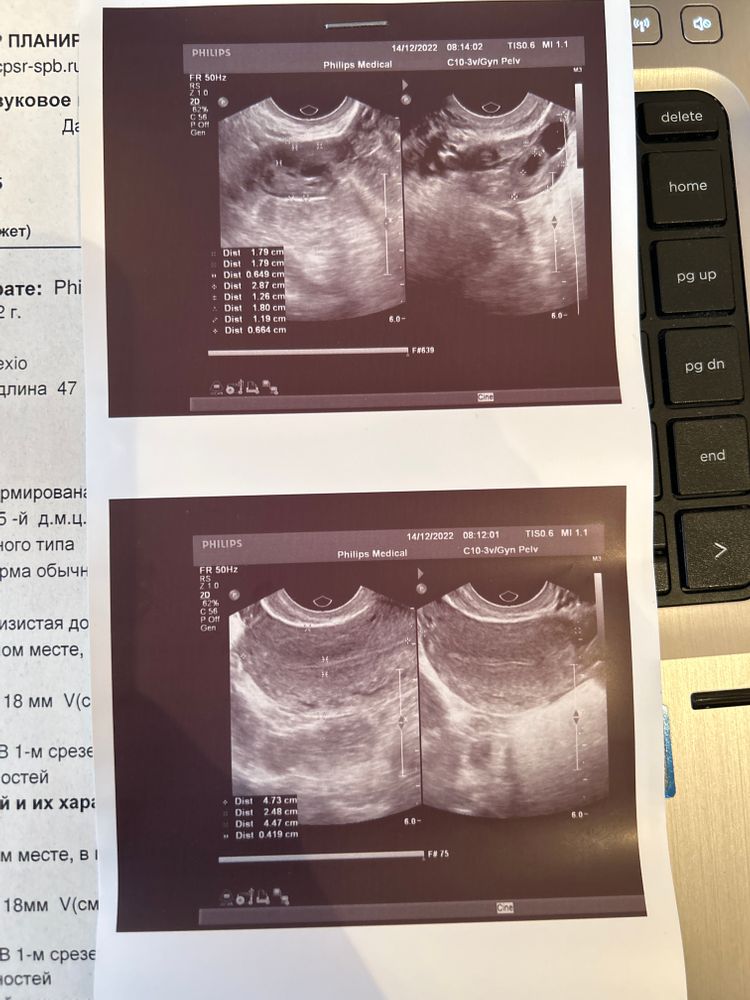

25 лет, по Узи по 2-3 яйцеклетки в срезе

Всем привет!) сегодня 5дц, пошла на Узи, где мне сказали, что в срезе по 2-3 яйцеклетки.. я в шоке, у меня еще год назад было 6-7… почему такое может быть? Амг сдала сегодня, посмотрим… что может влиять на кол-во яйцеклеток с резе? У кого так было?

Я делала фоликулометрию в течение месяца, в зависимости от аппарата УЗИ и дня цикла-плавают эти цифры.